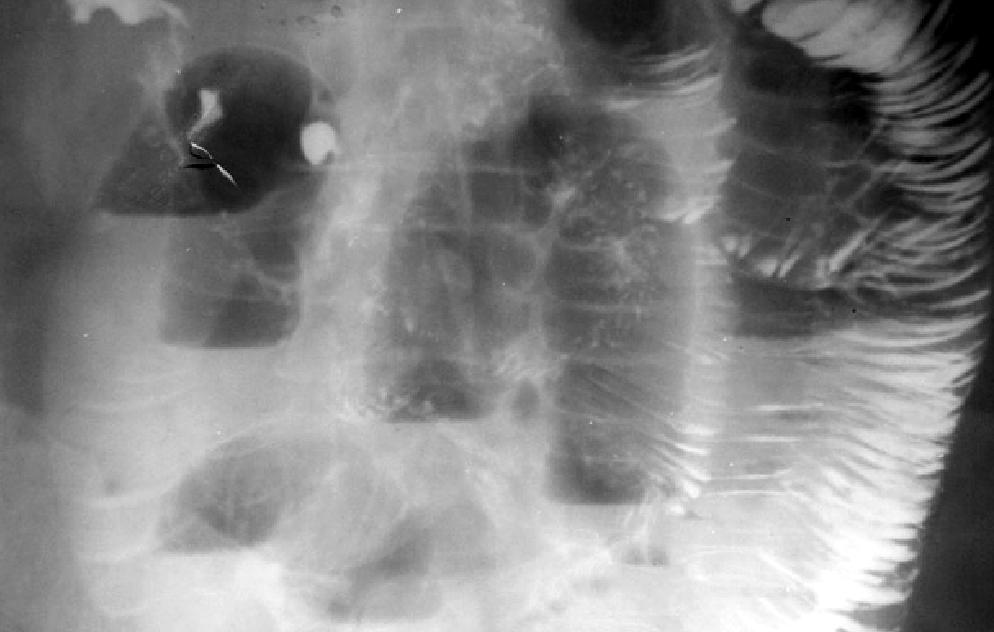

Общий анализ крови: Hb 96 г/л, лейкоцитов крови 18,2•109/л, п – 4%, с – 85%, л – 7%, м – 4%, СОЭ – 23 мм/час; общий анализ мочи: белок 132 мг/л, лейкоцитов 1–2 в п/зрения, эпителия – 3–5 в п/зрения, бактерии. При ультразвуковом исследовании патологии со стороны печени, желчных путей, поджелудочной железы, селезенки, почек не обнаружено. При обзорной рентгенографии органов брюшной полости выявляются множественные чаши Клойбера и Керкринговы складки в тонкой кишке.

Обзорная рентгенограмма органов брюшной полости

В правой подвздошной области нечетко определяется интенсивное гомогенное образование до 5 см в диаметре. Назначена консервативная терапия, на фоне которой улучшение не наступило. Отмечено появление защитного напряжения мышц передней брюшной стенки в эпи– и мезогастрии, положительный симптом Щеткина-Блюмберга. «Шум плеска» стал более выраженным.